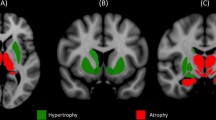

A significantly higher activation in ET−R patients with respect to ET+R patients was observed in precentral gyrus bilaterally (more widespread on the left side), in left postcentral gyrus, supramarginal gyrus, superior and inferior parietal gyri and medium temporal gyrus. In a lesser extent, right superior and inferior frontal gyri and left cerebellum resulted more activated in ET−R patients. A significant higher activation was also shown in left internal globus pallidus (GPi) (Table 3; Fig. 2).

ET+R patients did not show any significant more activated clusters with respect to ET−R patients.

The comparison between ET+R patients and ET−R patients showed, in the latter, a major activation especially in contralateral sensorimotor cortex, superior parietal gyrus and supramarginal gyrus. It could be related to the fact that the presence of resting tremor in ET+R patients could produce an increased BOLD effect during the rest phase of the task with respect to ET−R patients, who did not have any tremor in rest phase. So when BOLD effect of the rest phase was deducted from BOLD effect of the active phase of the task, signal change was lower in ET+R group compared to ET−R group. Interestingly, ET−R patients presented an increased GPi activation in comparison to ET+R patients suggesting a GPi dysfunction in ET+R patients. GPi has just been retained implicated in resting tremor generation in Parkinson’s Disease (PD). Actually in an EMG-fMRI study [54], a correlation between activity in the cerebello-thalamo-cortical network and the amplitude of resting tremor was reported, while GPi has been proposed as a trigger in the generation of a pathological oscillatory activity within the cerebello-thalamo-cortical network. The authors found also a positive correlation between clinical severity of tremor and dopamine depletion of GPi measured by [I-123]FP-CITSPECT. The role of GPi in PD tremor has been suggested by several imaging [55], electrophysiological [56], and pathological studies in humans [57] and primates [58, 59]. On the other hand, a recent postmortem study reported near-normal dopamine levels in ventral GPi of PD patients with prominent tremor [60]. No evidence so far on GPi in ET is available. Unfortunately, in our study, we cannot definitely establish a causal relationship between GPi dysfunction and resting tremor in part also because of the lack of a tremor quantitative analysis during the fMRI study. Thus, we could not correlate GPi activation with resting tremor severity. The evidence from our experience can only suggest a potential role of GPi in the resting component of ET, similar to resting tremor in PD.